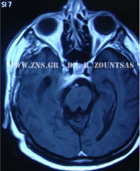

Ολική εξαίρεση μηνιγγιώματος πτέρυγας σφηνοειδούς

Ολική εξαίρεση μηνιγγιώματος λιθοειδούς αποκλίμματος